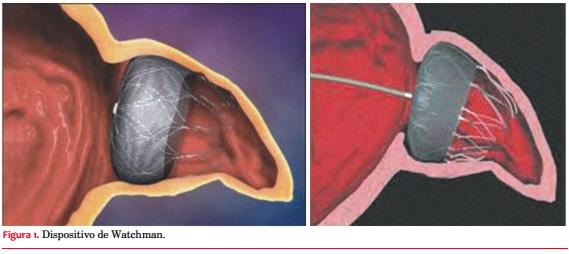

El segundo dispositivo fabricado para oclusión del AAI fue el Watchman, inicialmente desarrollado por la empresa Atritech Inc, Minnesota, y adquirido posteriormente por Boston Scientific en 2011 (figura 1).